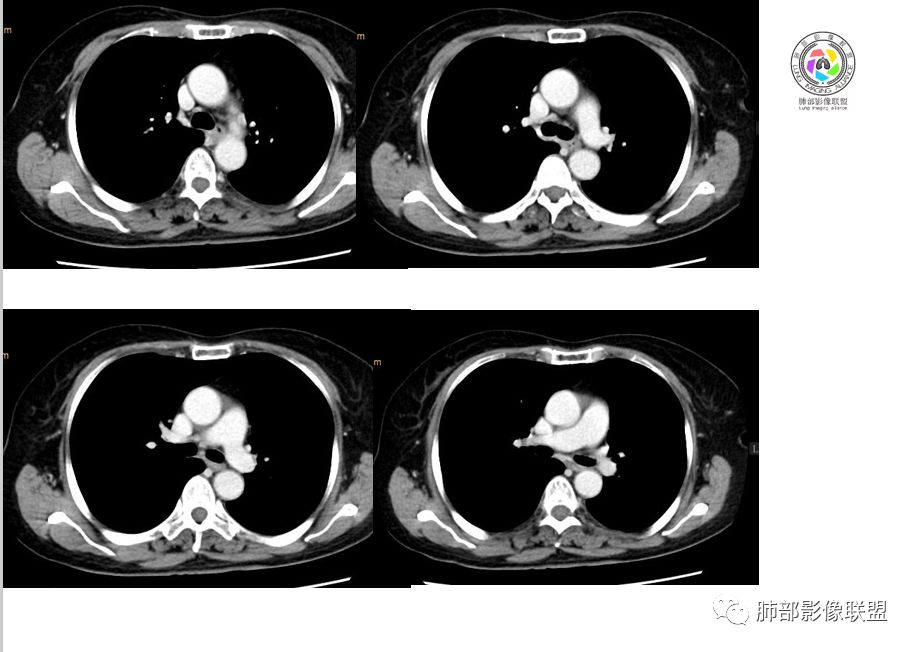

Coke with ice:PSP?M-Imaging :良性,PSPShelia:左肺下叶肿块,边缘光整,有血管贴边征,支气管受压推移,延迟强化,考虑PSP?鉴别类癌。不除外恶性

左手:老年女性,无特殊症状,左下肺类圆形结节,边缘清晰,增强见血管贴边,明显强化,无深分叶,无钙化,考虑pspForever:晨读病例病变与血管关系密切 确实psp首先考虑,类癌,腺癌,纤维瘤不能除外没意见:PSP,类癌待排徐超:psp

支气管无关,圆形,光滑,贴别血管稍粗,磨玻璃晕(出血),强化中度,支气管旁疑推挤非阻塞……良性

小木:考虑psp妞妞:支持PSP德芙~云味:考虑psp红日东升:支持PSP崔刚:强化具体CT值忘了标注,轻度强化

目前大家意见一致一米阳光:左肺下叶类圆形病灶,边缘清晰,密度均匀,无分叶毛刺等恶性征像,增强,病变明显强化,血管贴边支持PSP,鉴别类癌,后者弱强化,貌似有分叶南边:

崔刚:当时写报告看好像是支气管确实没堵,受压的改变。

横断位应该显示了这个支气管,当时记得特意考下来图了

M-Imaging :周围有黑边,错构呢?南边:如果明确没堵塞就好办这个最主要的就是这个支气管是否堵塞没堵塞,支持PSP杨泽锋:如果是气管腔内起源的那就要考虑类癌M-Imaging :不见明显冰山征,没有钙化南边:心里不是很踏实,就是没看到支气管全景Forever:强化如果不高 我还是考虑小细胞肺癌或者腺癌

崔刚:有个层面支气管在病灶周边Yiren  Sishui(厶水伊人):其实就是PSP与类癌的鉴别M-Imaging :Forever:如果分不清结构关系了 这个时候强化还是有很大参考价值M-Imaging :周围有黑边崔刚:没有钙化和脂肪,张老师是不是考虑错构瘤?徐超:黑边是想说错构瘤M-Imaging :是啊滴水海:psp也可Forever:不像 觉得ct值有点高。一般错构瘤ct值低于20,没有钙化

滴水海:有黑晕更支持pspM-Imaging :黑边代表局限肺气肿错构瘤,应该和血管没有关系,这例血管贴近毛勤香:考虑PSP或错构瘤,类癌代排南边:我的判断原则:支气管无关——良性、间叶来源良性,强化明显——PSP,尤为明显——糖瘤,不明显——错构瘤

wonderful:纵膈有吗徐超:隆突下没有肿大淋巴结。思路没问题,主要还是支气管的关系。还有CT值,有测量值最好。强化不同疾病范围不同,虽然有叠加Coke with ice:这个病灶好像有浅分叶,是否有鉴别意义呢南边:可能绕过去了。浅分叶没什么价值,深分叶有Forever:动脉期强化不太均匀 而且ct值不高我觉得有提示意义

M-Imaging :PSP强化应该达到一百多吧

1.肺内如此大小的周边较光滑的孤立结节影或块影,密度较均匀的,一般会想到硬化性肺细胞瘤、错构瘤、小细胞癌、大细胞癌、类癌,以及单发转移灶等。

2.边缘光整,坏死不明显,未显示阻塞性炎症或不张,女性患者,肺鳞癌不支持。

3.缺乏典型深分叶及毛刺,强化不显著,似乎也缺乏肺腺癌的影像学特点。

4.未见脂质密度及钙化,强化程度等均不支持错构瘤。

5.同样病灶轻到中度强化也不支持类癌及大多数的硬化性肺细胞瘤(血管瘤样区为主)。

后者不能排除,毕竟不是所有的硬化性肺细胞瘤强化都那么显著。

6.转移瘤缺乏相关临床支持。

7.病灶的形态及强化程度都不能排除小细胞癌及大细胞癌,纵隔尤其是隆凸下未见增大淋巴结似乎不符合小细胞癌等的生物学行为。